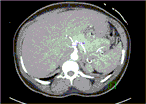

Infiltrating caecal carcinoma versus appendicitis with caecal phlegmon—can computer tomography differentiate them?

Henry To and others

Journal of Surgical Case Reports, Volume 2017, Issue 2, February 2017, rjx006, https://doi.org/10.1093/jscr/rjx006